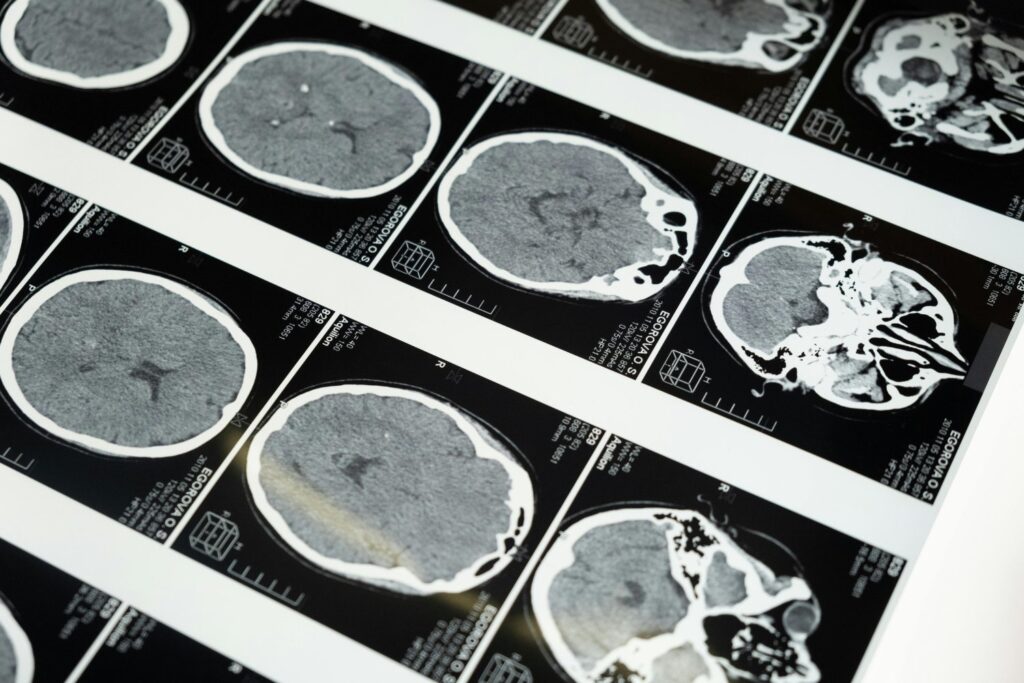

Un nuevo estudio comenzó a descifrar lo que ocurre en el cerebro de quienes trabajan jornadas maratónicas. Aunque se trata de una investigación inicial, sus hallazgos son tan sorprendentes como preocupantes. ¿Es posible que el trabajo excesivo esté alterando la estructura de nuestra mente sin que lo notemos?